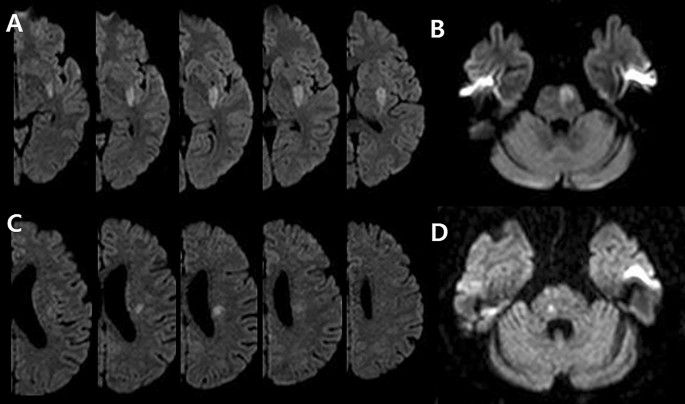

All patients underwent brain MRI and MRA within 24 h of admission via a 3.0-T magnetic resonance scanner (Achieva 3.0T; Philips, Eindhoven, the Netherlands). SSI was defined as a single lesion that did not involve the cerebral cortex but invaded the perforating artery in the middle cerebral artery, posterior cerebral artery, or basilar artery (e.g., striatocapsular, thalamic, or brainstem area)1. According to the location of the SSI lesion, we divided the involved vascular territory and the type of SSI1. The involved vascular territory was simply divided into anterior SSI and posterior SSI according to circulation. The type of SSI was divided into two types: proximal and distal. Proximal SSI was defined as an infarction adjacent to the parent artery and extended toward the basal surface of the parent artery1. Distal SSI was defined as an infarction that was located only in the distal area and was not in contact with the parent artery (Fig. 2)1. We measured the diameter (mm) and volume (mL) of the diffusion-weighted imaging (DWI) lesion, which are characteristics of SSI lesions. DWI volumes were measured quantitatively using Medical Imaging Processing, Analysis, and Visualization software (MIPAV version 11.0.0; National Institutes of Health, Bethesda, MD, USA). Volume measurement was performed using computer-assisted semi-automated technology on data obtained from converted files that are in DICOM format, similar to that in previous studies36.

SSI is a disease that exists as a single lesion from symptom onset to hospital discharge. Also, since the actual growth velocity of lesions is unpredictably complex, we simply assumed that they follow a linear trend. Based on this background, we hypothesized that approximate IGV could be measured by dividing the size of the lesion on the initial MRI by the time from symptom onset to image acquisition. That is, in simple terms, IGV can be calculated with the following formula: IGV (mL/h) = DWI volume (mL)/time to MRI (h) (Fig. 3). All radiological parameters were rated by two neurologists (K.-W.N. and H.-M.K.), and disagreements were resolved via discussions with a third rater (Y.-S.L.).

A representative example of how to calculate the infarct growth velocity. We quantitatively measured initial infarct volume using MIPAV version 11.0.0. program. The infarct lesions of each slice were delineated in a semi-automated way. After that, the program automatically calculated the volume by summing the lesion area of each slice. The initial infarct volume measured in this way was 1.97 mL, and MRI was conducted in this patient 1 h after symptom onset. Therefore, according to the formula, it is calculated that this patient had an IGV value of 1.97 mL/h.